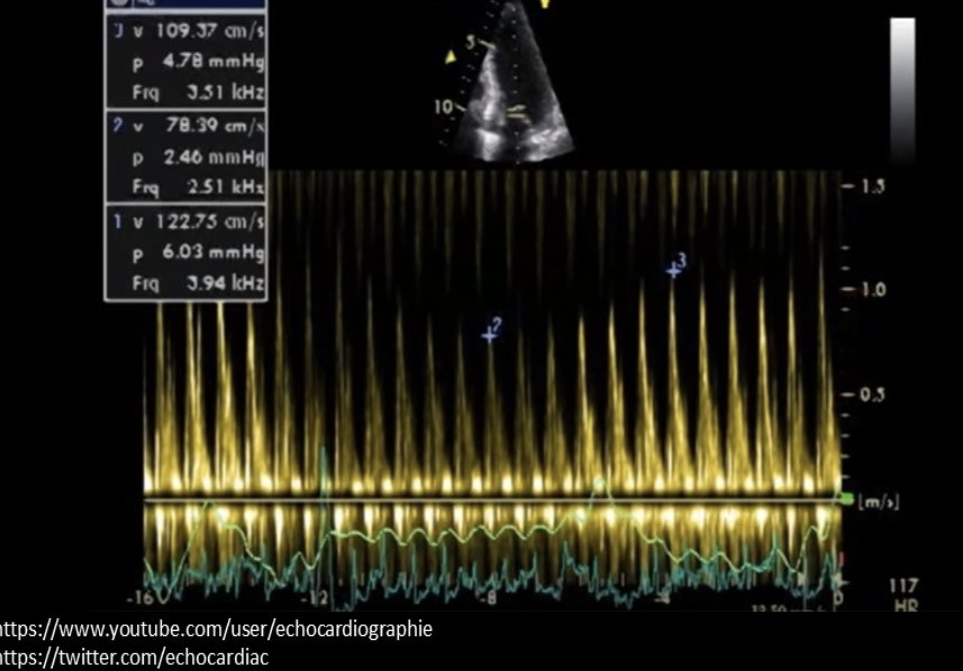

The calipers on the image are measuring?

Abnormal respiratory variation of the E velocities of the mitral valve due to cardiac tamponade

The Doppler tracing is consistent with which of the following cardiac abnormalities?

Constrictive pericarditis